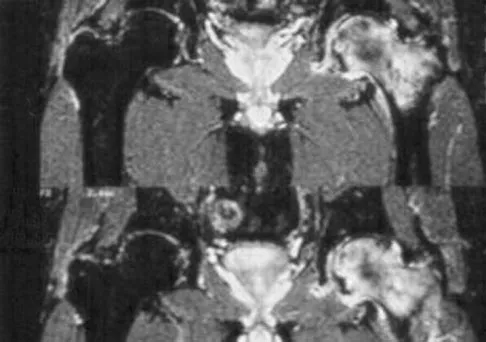

A 36-year-old woman with familial neurofibromatosis has an enlarging mass in the posterior thigh. The lesion has slowly increased in size and is now constantly painful. Pressure on the mass causes dysesthesias in the foot. Figures 44a through 44c show T1-weighted, STIR, and T1-weighted fat-saturated gadolinium scans, respectively. Figure 44d shows a PET scan. What does this lesion most likely represent?

Explanation

The images reveal a large mass in the posterior thigh arising from the sciatic nerve. The lesion is edematous, and the gadolinium image reveals rim enhancement, suggesting necrosis, given that the STIR image is not uniformly bright as would be seen in a cystic lesion. The PET scan has increased uptake, in this case a standard unit value (SUV) of greater than 2.0. These findings are all very suggestive of a malignant process. The history of neurofibromatosis makes a malignant peripheral nerve sheath tumor, or neurofibrosarcoma, the most likely diagnosis. The term "peripheral nerve sheath tumor" has replaced neurolemmoma and schwannoma. Menendez LR (ed): Orthopaedic Knowledge Update: Musculoskeletal Tumors. Rosemont, IL, American Academy of Orthopaedic Surgeons, 2002, pp 225-230.